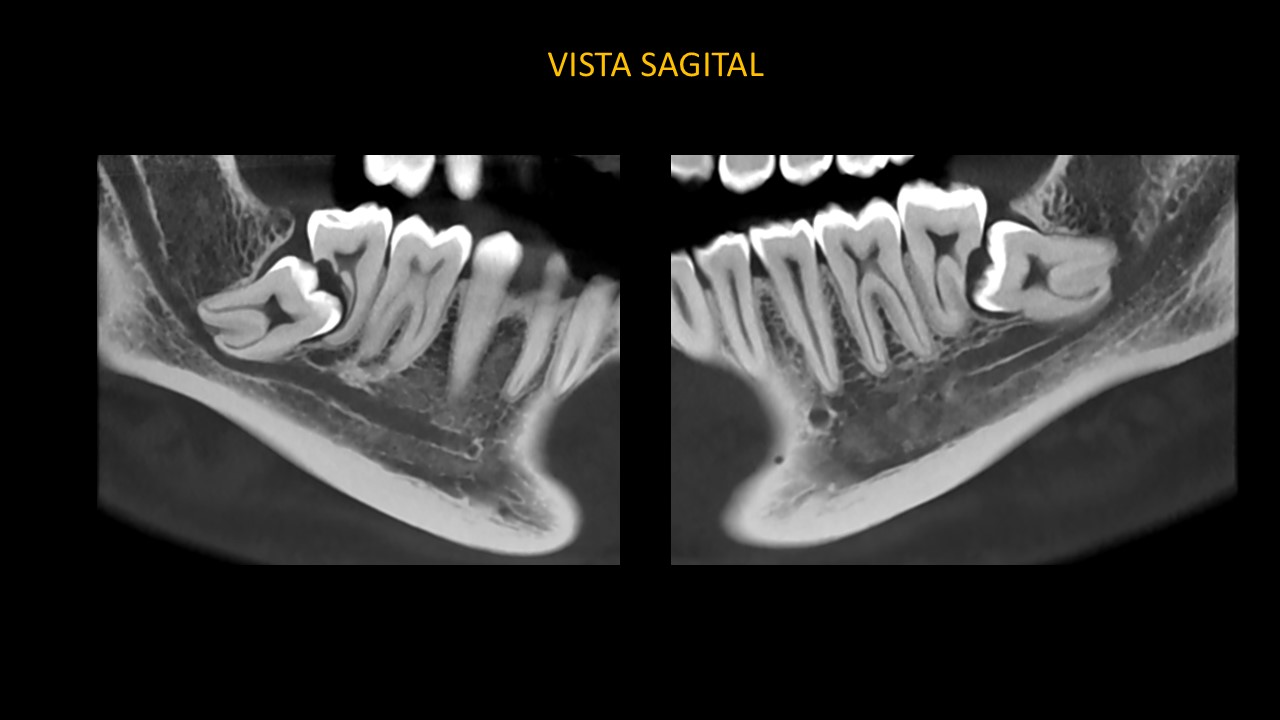

Figura 3

En las vistas sagitales (Figura 3), evidenciamos la extensión de corona de pieza 38 hacia distal de pieza 37, en correlación con imagen hipodensa peri coronaria, se extiende hacia el reborde alveolar y cortical superior del conducto dentario inferior. Se observa la corona de pieza 48 hacia distal de pieza 47, en correlación con imagen hipodensa peri coronaria, se extiende hacia el reborde alveolar y tercio medio – apical de pieza 47.